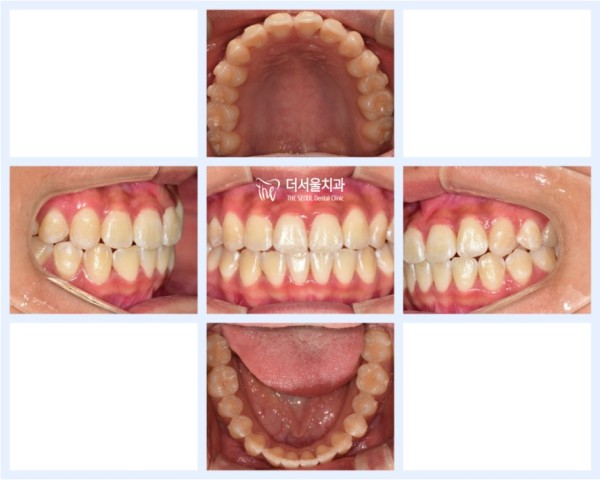

이 학생은 앞니가 삐뚤어져 있어서 이 부분을 개선하고 싶었습니다.

저희 성남치과 더서울치과 원장님들의 유튜브를 보고 찾아오셨다고 하시는데요.

10대때 치아교정을 하게되면 성장기이기 때문에

다른 수술을 하지 않아도 악궁확장장치 등을 사용하여

치료를 있다는 장점이 있답니다.

This student wanted to improve this part because his front teeth are crooked.

I heard that you came after watching the YouTube of the directors of Seongnam Dental Clinic The Seoul Dental Clinic.

If you get braces when you're a teenager, it's a growing season

You don't have to perform any other surgery, but you can use the arch extension device

It has the advantage of being able to treat it.

이 학생은 초기 예상한대로 약 1년정도의 교정기간이 걸렸으며

최종 모습을 보면 앞니가 잘 펴져있는것을 확인할 수 있습니다.

This student took about a year of proofreading as expected

If you look at the final appearance, you can see that the front teeth are well spread out.